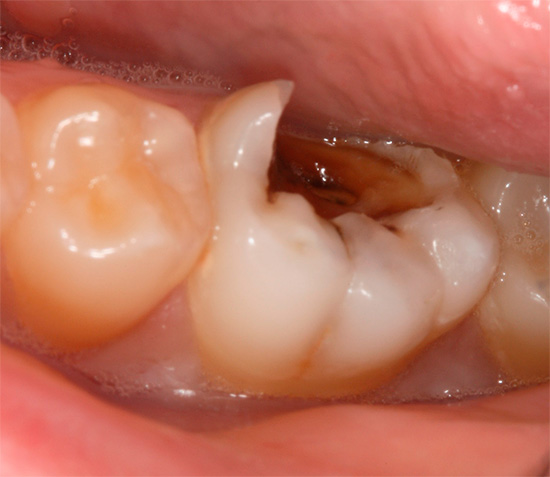

In generale, la pulpite è un'infiammazione del fascio neurovascolare all'interno della corona del dente e dei canali radicolari. Se in alcuni casi di polmonite acuta (focale) è possibile interrompere il processo infiammatorio e trattare il dente in modo conservativo, cioè senza rimozione del nervo, quindi la pulite cronica è quasi sempre una forma irreversibile della malattia. In questo caso, una graduale degenerazione della polpa avviene all'interno del dente: la formazione di tessuto fibroso, la necrosi (necrosi) o la proliferazione del fascio neurovascolare fino a riempire la cavità che porta alla patologia.

Le forme croniche di pulpite sono causate da microrganismi patogeni, nonché dai loro prodotti metabolici, e nella maggior parte dei casi la malattia è provocata dalla carie profonda o da un trattamento improprio: violazione della tecnica di lavorazione del dente, scarsa pulizia della cavità cariata, riempimento mal posizionato, ecc. "Trigger" meno frequenti dello sviluppo della patologia sono:

L'ispezione visiva del dente con una sonda appuntita e uno specchio fornisce circa il 50% delle informazioni necessarie. In termini di aspetto della cavità, indolenzimento del suo fondo, comunicazione con la camera pulpare (il luogo in cui si trova il "nervo"), si può già ipotizzare la pulite cronica.

Se c'è un messaggio con una cavità cariata e compaiono dolore e sanguinamento quando si sondano con una sonda acuta, allora con un alto grado di probabilità è cronico pulite fibrosa. Con un cambiamento nel colore dei denti, l'aspetto di un'ombra grigia, con una grande quantità di tessuto cariato ammorbidito nella cavità del dente, quando il "nervo" viene parzialmente distrutto e il dolore si verifica solo quando si sondano i canali, allora è molto probabilmente una polpite cranica cronica. La comparsa di tessuto troppo cresciuto all'interno della cavità in combinazione con l'indolenzimento quando lo sondano il più delle volte indica una polpite ipertrofica cronica.